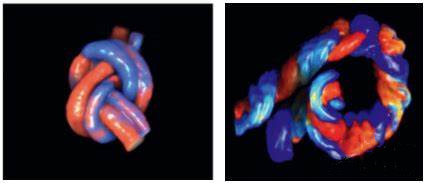

一、什么是脐带绕颈?

脐带绕颈(Nuchal Cord)指脐带环绕胎儿颈部1周或以上的现象,是孕期较常见的情况。据统计,约20%-30%的孕妇会在产检中发现胎儿存在脐带绕颈。

二、为什么会发生脐带绕颈?

胎儿在子宫内活动时(如翻滚、伸展)可能使脐带缠绕颈部,常见原因包括:

1.脐带过长(正常长度30-100cm)

2.羊水过多导致胎儿活动空间大

3.胎儿体型较小

三、脐带绕颈危险吗?

大部分是安全的:脐带富有弹性且表面有胶质保护,松散绕颈通常不影响血流。

需警惕的情况:绕颈圈数多(≥3圈)或脐带过紧、脐带打结,可能影响氧气输送(需胎心监护确认)。